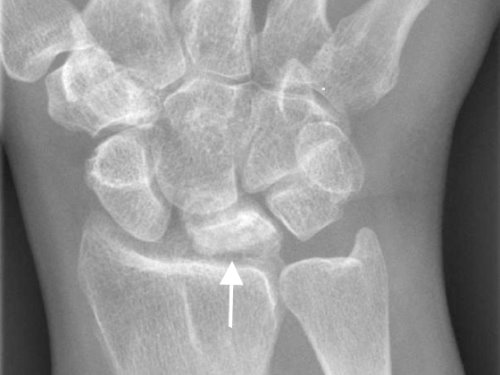

Lunatomalacia

Lunatomalacia. Typical finding in lunatomalacia (Kienböck's disease) on plain x-ray film. The lunate bone is sclerotic and slightly collapsed.